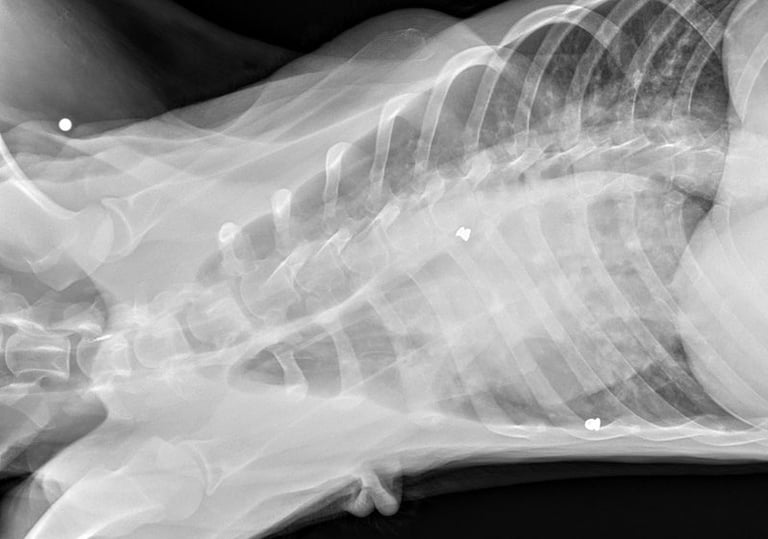

Cooper’s story is heartbreaking. He was found near the woods in Hilliard, painfully thin and carrying the scars of a cruel past. X-rays revealed he had been shot with BB guns, and four pellets are still lodged in his body.